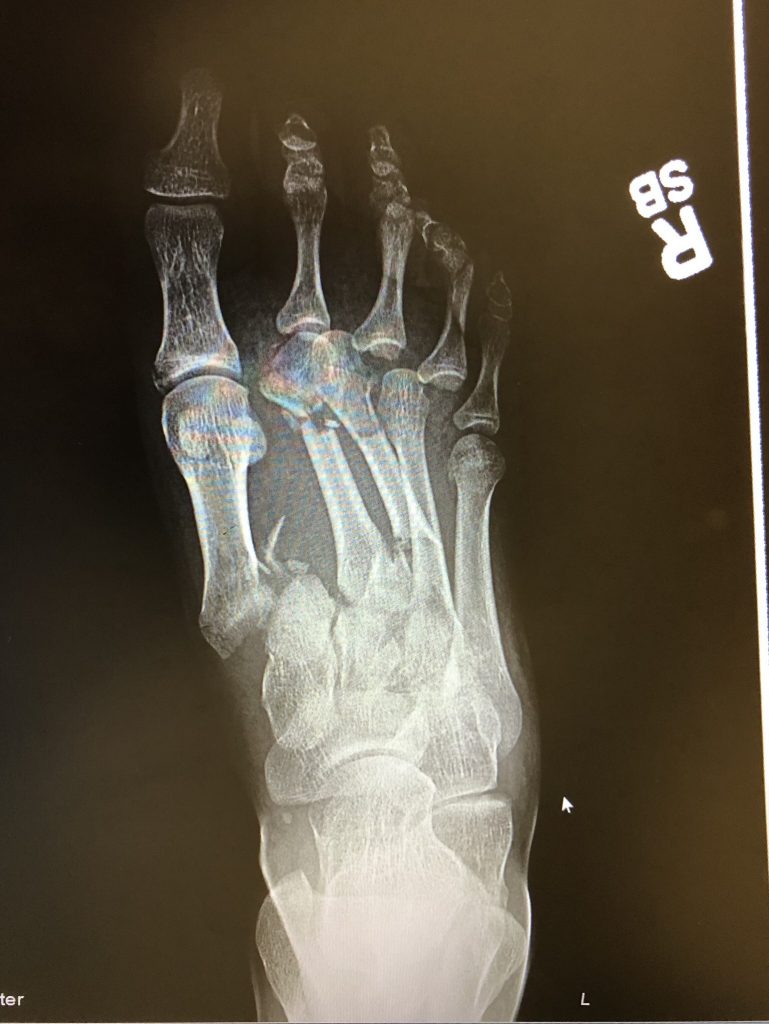

Back on 4th of July weekend I was riding motocross at a track in North Carolina. I over rotated the bike mid-air and lost control and crashed having the bike land on my right foot. I knew as soon as I crashed it was going to be a long healing process and it was going to be little while until I could get back on the bike and ride again. With the help of Dr. David S. Levine and everyone else who helped me at HSS I was back on the bike within 6 months after a serious Lisfranc injury. HSS is truly amazing and for sure life changing. I'm so glad I chose HSS to get me Back in the Game!

I've attached the x-ray after my crash and a picture after I was cleared to get back on the bike.